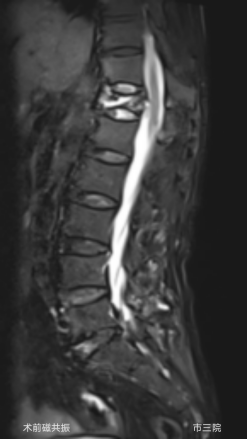

外二科收治了一位82岁的老年女性患者,患者摔倒后因腰部疼痛不能下床活动,在家长期卧床5个月,期间外用膏药,效果不佳,老人虽八十多岁,但受伤前身体硬朗,自己能够洗衣、做饭、赶集等,自从摔伤后不见好转卧病在床,子女们轮流照顾老人,打破了原本平静的生活,眼见老人下不了床子女们心急如焚,四处打听创伤小恢复快的治疗办法,经人介绍来到我院外二科就诊,磁共振检查显示患者胸12椎体压缩性骨折,椎体压缩性骨折已经5个月了仍未愈合,已经形成kummell 病,骨折基本不能愈合,此病首选经皮穿刺骨水泥注射椎体成形术治疗,创伤小、可迅速恢复自理生活,经与患者及家属沟通后同意手术治疗,就诊当天就办理了住院,住院后赵东主任医师对老人进行了全面查体,对老人家原本患有“冠心病、糖尿病”,积极联系内科会诊,完善术前检查做好充分术前准备。术中C型臂准确定位后,局麻下5mm皮肤切口,赵东主任医师顺利打入椎体骨水泥,韩克伟医生询问患者有无不适,患者诉腰部疼痛症状消失,术后第二天,患者佩戴胸腰护具下床独立行走,露出了久违的笑容。